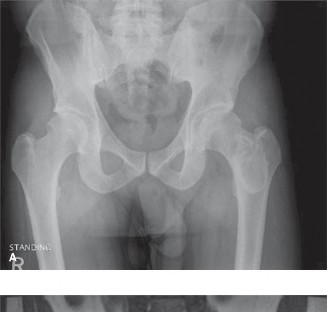

A 72-year-old female presents with progressive bilateral hip and pelvic soreness as well as back pain and hea…